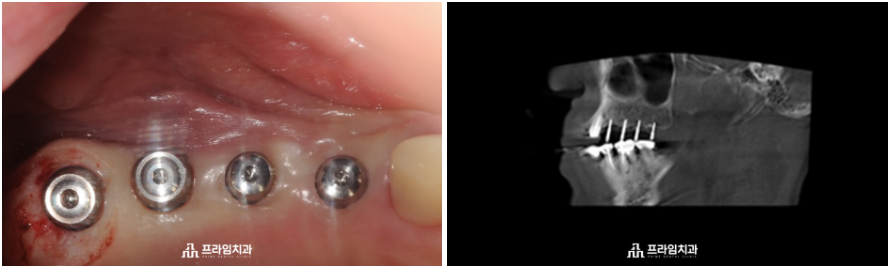

매직 코어 임플란트는 임플란트를

구성하고 있는 지대주와 인공 치근이

일체.형으로 형성되어 잇몸뼈의

폭이 좁거나 상태가 좋지 않은 경우에도

골이식이나 골성형 과정을 줄여

식립할 수 있는 최소침습 임플란트를 말합니다.

.

한 번의 수술 과정으로

본래 자연치아의 기능과 심미성까지

동시에 회복할 수 있도록 해준다는

장점을 가지고 있으며, 식립 시 나사선

사이의 Interthread bone이 손상되지

않아 골 회복에 유리하고 최소침습으로

일반 임플란트 보다 골 유착이 유리합니다.

환자분께서는 치과 치료에 대한

공포와 골다공증을 앓고 계셔서

걱정을 많이 하셨지만 의료진과의

충분한 상담을 통해 큰 무리 없이

임플란트 식립을 진행할 수 있었습니다.